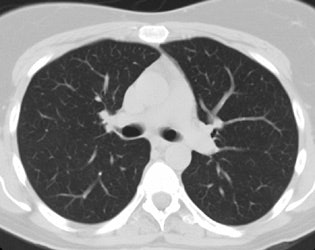

Rapidly enlarging lung cancer: The patient shown below was being followed for small lung nodules and prominent mediastinal lymph nodes. A chest CT in 2/2006 (left image) was stable to prior exams. A follow-up chest CT 10 months later (12/2006- right image) revealed a new, lung cancer in the right upper lobe. Extensive metastatic disease had already occurred. Such rapidly growing cancers may not be detected on screening CT exams. The small lung nodules (not shown) were again noted to be unchanged. |